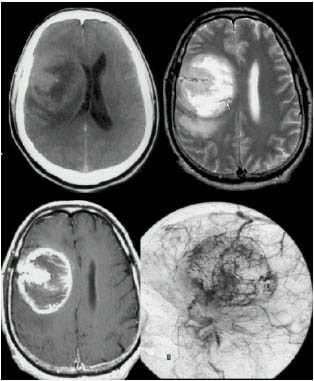

МРТ с контрастированием пациента с глиобластомой левой височной доли до операции, Т1-взвешанное изображение.

МРТ с контрастированием того же пациента через 12 часов после операции, Т1-взвешанное изображение (опухоль удалена тотально).

Глиобластома - наиболее злокачественная и агрессивно растущая из всех глиальных опухолей, является самой частой первичной опухолью ЦНС. Мужчины заболевают примерно в полтора раза чаще, чем женщины. Макроскопически опухоль представляет собой образование гетерогенной структуры с центральными или множественными очагами некрозаа, часто наблюдаются внутриопухолевые кровоизлияния. При гистологическом исследовании определяется резко выраженная атипия клеток с высокой митотической активностью. Четкой границы между опухолью, зоной отека и окружающей мозговой тканью нет. Симптомы повышения внутричерепного давления обычно быстро нарастают; типичны нарушения личности или появление выраженной очаговой симптоматики. Глиобластома чаще локализуется в глубинных отделах полушарий мозга с прорастанием в мозолистое тело с распространением на оба полушария в форме «бабочки». На КТ плотность опухоли весьма гетерогенна.

Центральная зона низкой плотности представляет некроз, контрастное усиление выражено в виде окаймляющего кольца с неровным внутренним контуром. В опухоли нередко отсутствует узловой компонент и она растет инфильтративно, имея многодолевое распространение. При МРТ регистрируются участки гипо-, изо- и гиперинтенсивного сигнала от стромы опухоли, некроза, кист и кровоизлияний.